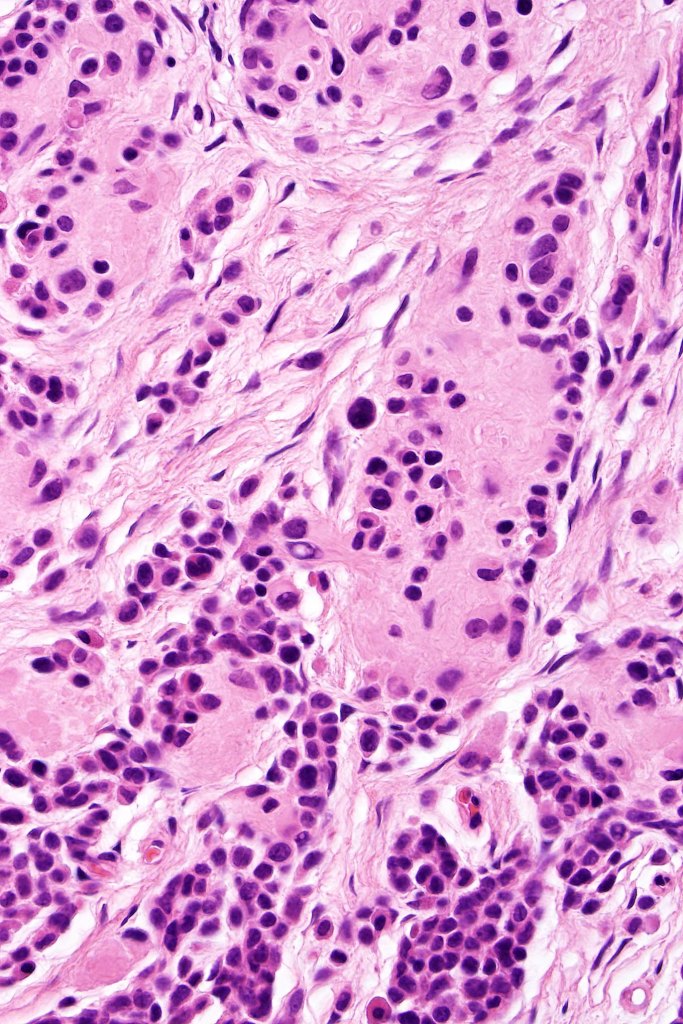

This is uncommon and presents clinically with a history of recent change in color of a common or less often congenital nevus causing concern for melanoma by the clinician. Some, but not all are probably deep penetrating and combined nevus variants. Others may represent follicular type-A cell nests. It is characterized by the presence of deep nest(s) of type -A nevus cells surrounded by & with overlying type-B nevus cells.